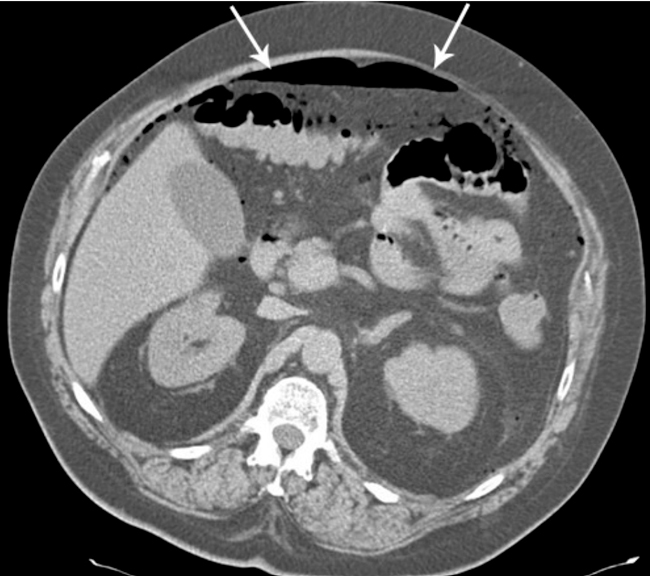

Perforation, Free Air in the Abdominal Cavity

Perforation, free air in the abdominal cavity.

Picture: Dean K, Sonninen P. [Imaging for acute abdomen]. In: Roberts P, Alhava E, H�ckerstedt K, Leppäniemi A (toim.). [Surgery]. Helsinki: Duodecim Publishing Company Ltd, 2010